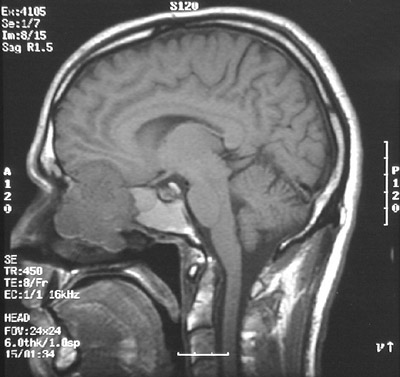

This MRI scan in sagittal view demonstrates an olfactory neuroblastoma filling the nasopharyngeal region, eroding the orbital plate superiorly, and extending to the inferior frontal lobe.